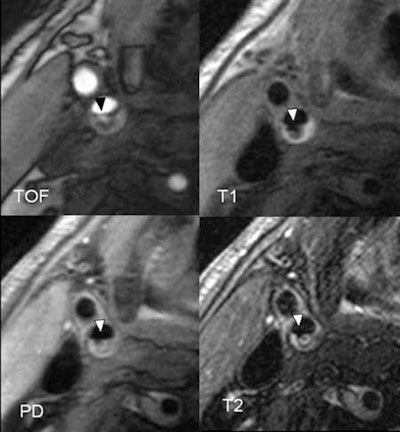

To find out, a high-resolution MRI examination of the carotid arteries is carried out within seven days of the stroke. After a year, this examination is repeated, and a brain MRI is performed. For black blood MRI, the signal from the blood flow is suppressed; the same sequences are in use for cardiac imaging. Dedicated surface coils are used; the so-called Blood Imaging Group in Munich, a team of graduate students, generates the necessary sequences for the study in the 3-tesla device. Imaging is done together with physicians and takes approximately 20-25 minutes for the carotids.

Based on this imaging method, type VI plaques can be identified. These plaques have a history of bleeding, clot formation, or rupture. One year after the launch of the study, data from the first 50 patients have now been evaluated to produce interim results.